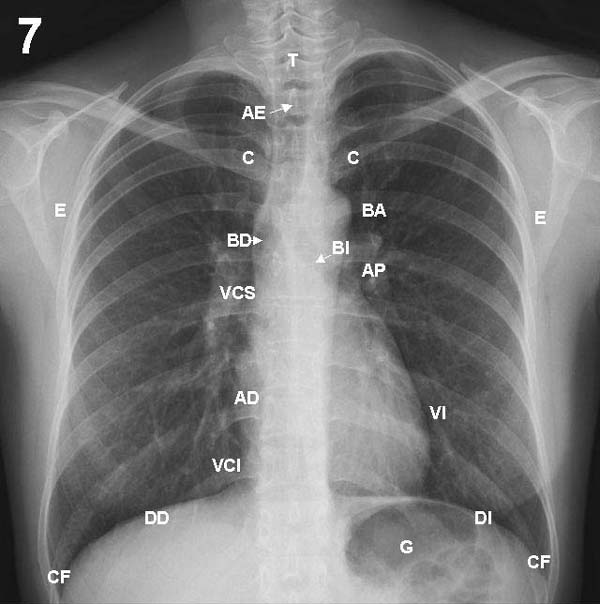

Pase primero a la placa 7 (frontal) y localice en ella las marcas correspondientes

a los elementos que a continuación se indican. Después haga lo

mismo con la placa lateral 8.

PLACAS 7 Y 8

Paredes del tórax

COLUMNA VERTEBRAL: los cuerpos vertebrales se ven en forma borrosa,

y las apófisis espinosas (AE), dispuestas a lo largo de la línea

media, se aprecian mejor en la parte alta del tórax, perdiéndose

detrás del corazón. En la proyección lateral las

vértebras se ven más claramente, viéndose más

blancas las superiores por la sobreposición de las masas musculares

de la cintura escapular.

COSTILLAS: por su trayecto oblicuo los arcos posteriores de las

costillas se proyectan varios centímetros más arriba que

sus extremos anteriores, que son los más fáciles de individualizar

para contar las costillas. Sus bordes son aproximadamente paralelos, y

los espacios intercostales son iguales a ambos lados del tórax.

ESTERNON: se ve en su totalidad en la proyección lateral

(ET), mientras que en frontal sólo se ve la zona del manubrio por

encima de la extremidad de la segunda costilla. Ocasionalmente puede aparentar

un ensanchamiento de la parte alta del mediastino.

CLAVICULA: es importante individualizar sus extremos internos (C)

en relación a las apófisis espinosas para verificar si la

placa esté bien centrada.

ESCAPULA: al tomarse una radiografía, los brazos se ponen

en posición tal que las escápulas (E) son desplazadas fuera

del campo de proyección de los pulmones, pero generalmente es posible

ver su borde interno proyectado sobre éstos.

DIAFRAGMA: En inspiración profunda la parte más alta

de la cúpula diafragmática derecha (DD) coincide aproximadamente

con el extremo anterior de la 6» costilla. Debido al peso del corazón,

la cúpula izquierda (DI) está 1,5 a 2,5 cm más abajo

en el 90% de los sujetos normales. Usualmente las cúpulas son regularmente

redondeadas, pero pueden presentar lobulaciones. A ambos lados contactan

en ángulo agudo con las paredes costales formando los senos costofrénicos

laterales (CF). Hacia la línea media, la cúpula derecha

termina formando con el corazón el ángulo cardiofrénico,

mientras que a la izquierda puede seguirse por varios centímetros

dentro de la sombra cardíaca. Uno a dos cm bajo el diafragma izquierdo

se observa la burbuja de aire del estómago (G), relación

que sirve para reconocer la posición de pies en la placa frontal,

TRAQUEA: en la placa frontal se ve como una tenue columna aérea

(T) que baja por la línea media, desviándose ligeramente

a la derecha a nivel del cayado aórtico. En la radiografía

lateral es levemente oblicua de delante a atrás.

BRONQUIOS PRINCIPALES:

en la placa frontal, un poco por debajo del nivel del botón aórtico,

se separan las columnas aéreas de los bronquios derecho (BD) e

izquierdo (BI), formado una carina de ángulo variable entre 50

y 100%.

MEDIASTINO: Los órganos centrales del tórax forman una

silueta característica en la placa frontal, cuyo borde derecho

está formado de arriba abajo sucesivamente por el tronco braquiocefálico

derecho, la vena cava superior (VCS), la aurícula derecha (AD)

y una pequeña parte de la vena cava inferior (VCI). El borde izquierdo

empieza arriba con la arteria subclavia y sigue con la prominencia del

botón aórtico (BA). En la parte media se proyecta el tronco

de la arteria pulmonar(AP), parte de la aurícula izquierda y finalmente,

el ventrículo izquierdo (VI), que forma un arco fuertemente prominente.